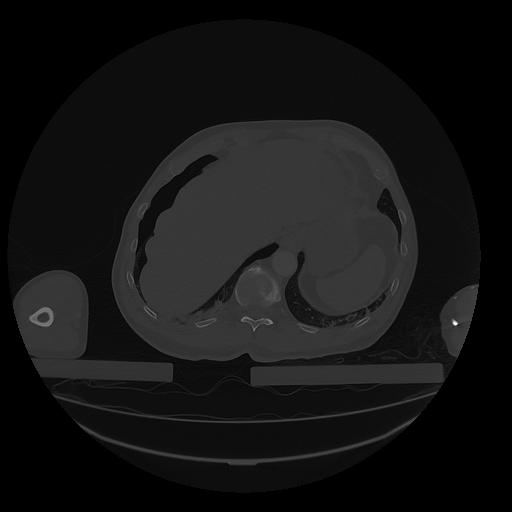

31 PULMON,CE,Vol,1.0,PULMON,,